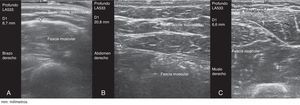

Este estudio prospectivo observacional transversal incluyó a 117 pacientes con AR (n=59) y EspA (n = 58) en tratamiento con anti-TNF sbc, autoadministrado por el paciente durante mínimo 6 meses. En todos los pacientes se midió el grosor del TCS en los sitios recomendados para la inyección sbc (brazos, abdomen, muslos), independientemente del sitio de preferencia para la autoadministración, utilizando ecografía en escala de grises (ecógrafo equipado con transductor lineal multifrecuencia de 6-18MHz). La medición ecográfica del TCS se realizó siempre con el mismo método: paciente en posición de sedestación, y aplicación de gel entre la sonda y la piel para evitar la compresión del TCS por la sonda (fig. 1); la sonda se colocó de forma transversal y longitudinal, del lado derecho e izquierdo, en los sitios recomendados para la inyección sbc. Posteriormente, calculamos la media entre ambas mediciones.

El grosor medio del TCS fue significativamente mayor en el abdomen (media±DT, 24,7±14,3mm) que en el muslo (11,6±4,9mm) y que en el brazo (9,1±4,5mm) (p<0,0005).

El grosor del TCS puede ser importante para seleccionar la longitud de la aguja y la técnica de inyección7-9, para asegurar la entrada del fármaco a TCS y no IM8,10, que a su vez influye en la respuesta terapéutica. La ecografía de alta frecuencia permite mediciones directas del grosor de TCS en cualquier sitio anatómico y es inofensivo, fácil y rápido. Nuestros resultados mostraron un porcentaje significativamente menor de remisión en el grupo que se autoadministraba anti-TNF en brazo (n=12), con un grosor significativamente menor del TCS (grosor TCS brazo en mm; media±DT, 7,5±2,3).